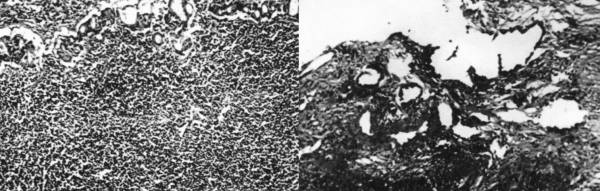

The pathologic examination of the endoscopic biopsies showed intestinal metaplasia and a dense lymphocytic infiltration of the mucosa giving the impression of a lym- phoma. In a particular tissue fragment, anomalous adeno- matous malformations with dysplastic epithelium were noted, suggesting the existence of a gastric adenocarci- noma (Figure 1).